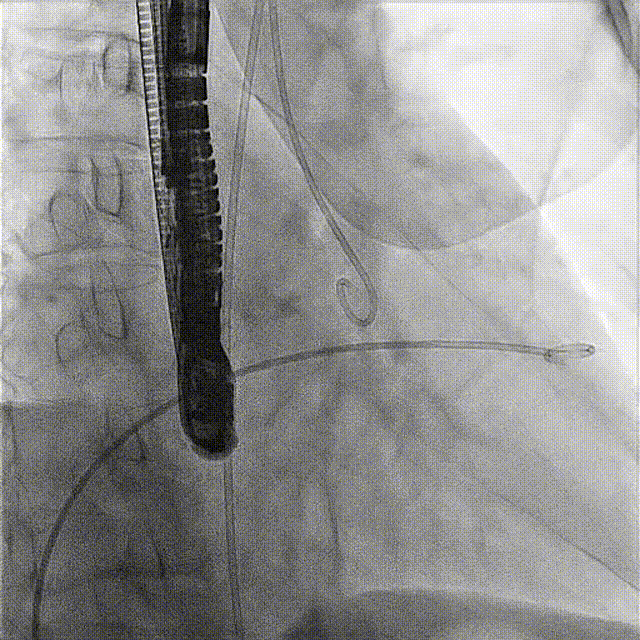

術前DSA

術前經過全面系統的評估后,考慮患者存在高齡、心功能減低、三尖瓣瓣環重度擴張(三尖瓣極重度反流)等高危因素,因此廈心結構心團隊聯合超聲心動、麻醉及護理團隊,制定了詳盡的圍術期治療方案及術中治療難點預案。術中,由王焱院長主刀,在蘇茂龍主任超聲心動團隊的輔助,上海市第一人民醫院陸方林主任的協助下,僅用時30分鐘,即順利完成了三尖瓣原位置換的手術。術中患者血流動力學穩定,術后即刻顯示LuX-Valve Plus瓣膜位置良好,固定穩定,瓣膜功能正常,無瓣周漏。

術后DSA